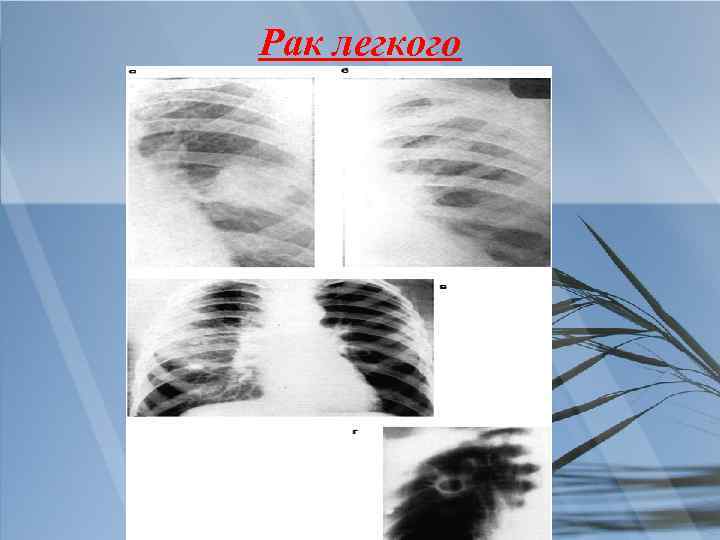

При проведении дифференциального диагноза пневмонии следует исключить другие заболевания, сопровождающиеся притуплением перкуторного звука при сравнительной перкуссии лёгких, кашлем и болями грудной клетки: острый бронхит, туберкулёз и рак лёгкого.

Рак легкого